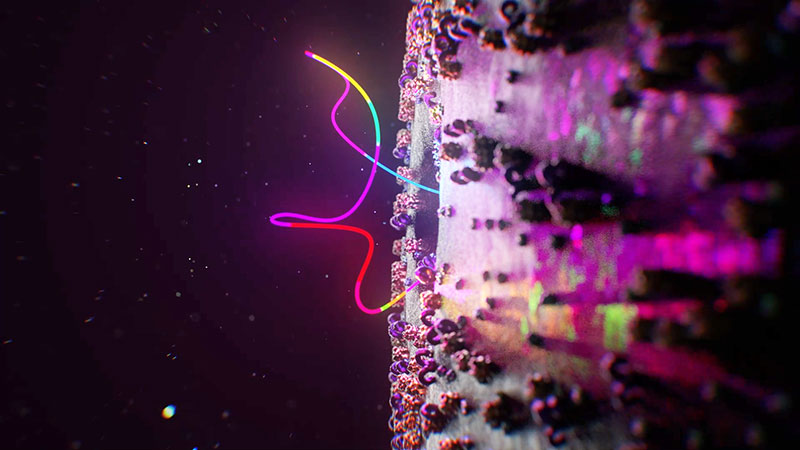

New Therapy

Nanodecoys project with North Carolina State University

One of the first Microverse projects to use the workflow was an animation conveying a new therapy to treat COVID-19 that was developed by researchers at North Carolina State University and UNC-Chapel Hill. Project frames were often rendered and returned long before they were needed, avoiding down time and allowing lead animator Amanda Manowski to remain immersed in the creative process.

A lot of planning went into their approach to the overall look, the texture of the membranes, for example, and how light reacts with the membranes and other critical surfaces. The studio’s animators typically work in Maxon Cinema 4D on local workstations and render with Redshift on Conductor. Character animation techniques were used to help viewers differentiate between and identify the various particles and tissues in an animation. Amanda also had specific qualities in mind for the lighting effects and reflections.

Multiple Applications

She needed to use multiple applications to develop the geometry -- Cinema 4D X-Particles dynamics to produce and understand the general shape, and ZBrush to build out the detail. The Redshift renderer influenced every 3D scene, of course, and as well as the base materials and lighting, she built certain effects and AOV outputs through its material nodes, such as the flashing effects needed for one scene. Red Giant tools were used to add glows, and compositing was done in After Effects.

Nanodecoys project with North Carolina State University